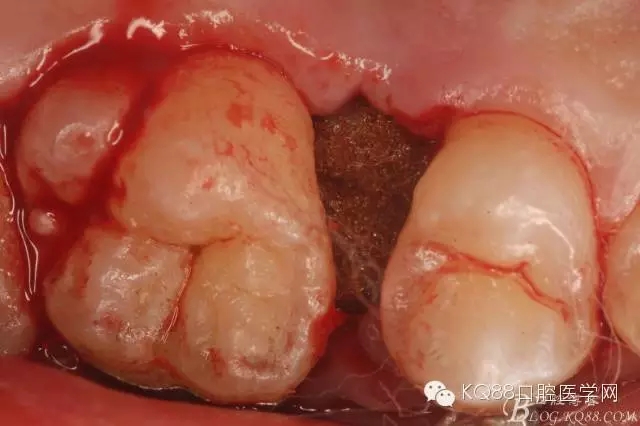

图21.相邻牙齿毫发无损,牙槽窝形态正常,无破坏。

图22.牙槽窝内放置胶质银止血海绵